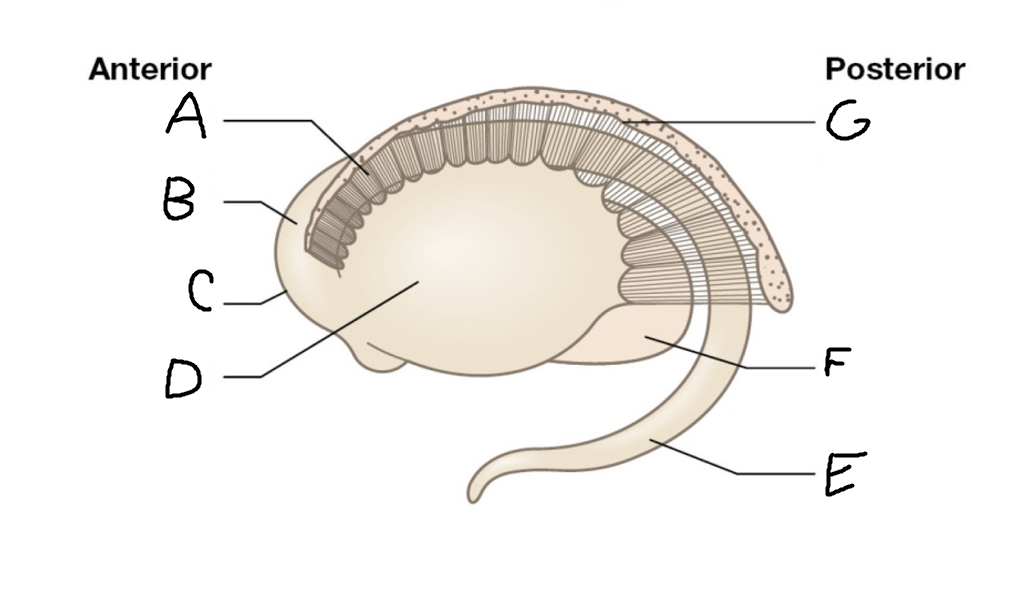

A

caudate nucleus head

C

caudate tail

D

globus pallidus (internal segment)

E

globus pallidus (external segment)

F

putamen